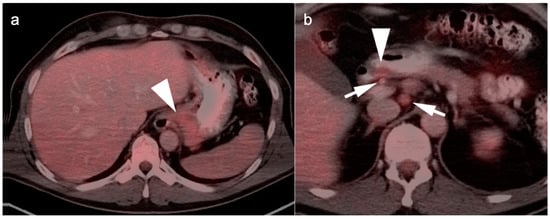

6. Gallbladder Carcinoma